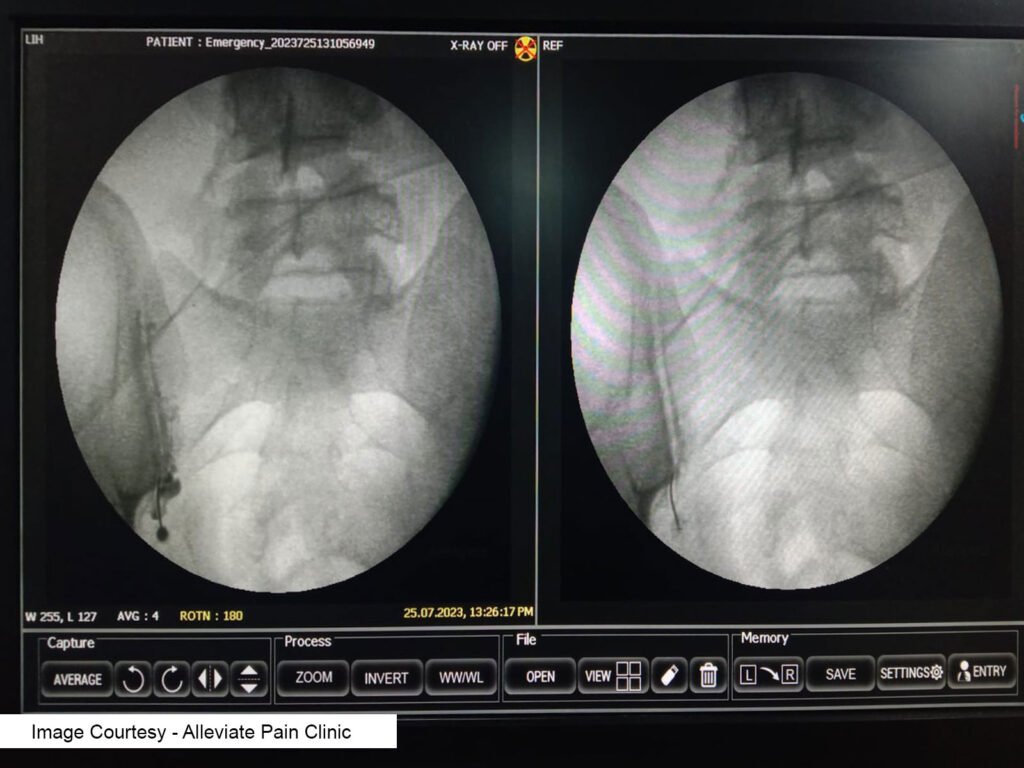

Radiofrequency Denervation of Sacroiliac Joint

Radiofrequency denervation, also known as radiofrequency ablation, involves using heat to disrupt the nerve fibers transmitting pain signals from the sacroiliac joint. Research, including a study in the Journal of Pain Research, suggests that radiofrequency denervation can provide significant and long-lasting pain relief in patients with sacroiliac joint pain (Patel et al., 2013).